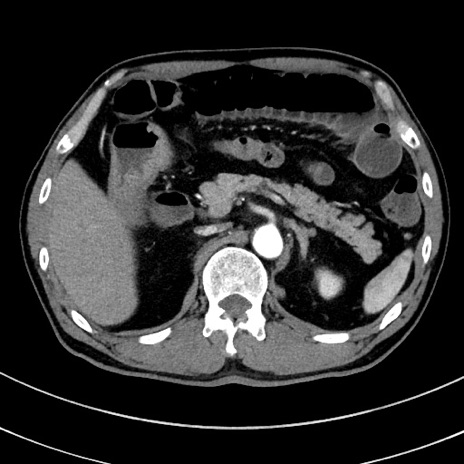

症例8(横断像)

【症例】 60歳代男性

【主訴】 黒色吐物

【現病歴】 4日前から嘔気自覚、2日前の朝食後にも嘔気あり、自分で手で嘔吐反射起こし嘔吐したところ血が混ざっていたため受診。

【既往歴】 5年前汎発性腹膜炎を伴う急性虫垂炎で手術、高血圧、前立腺肥大症、高脂血症

【身体所見】 腹部正中に手術癩痕あり 腹部平坦・軟圧痛なし膨満感あり

【データ】WBC 8400、CRP 4.54